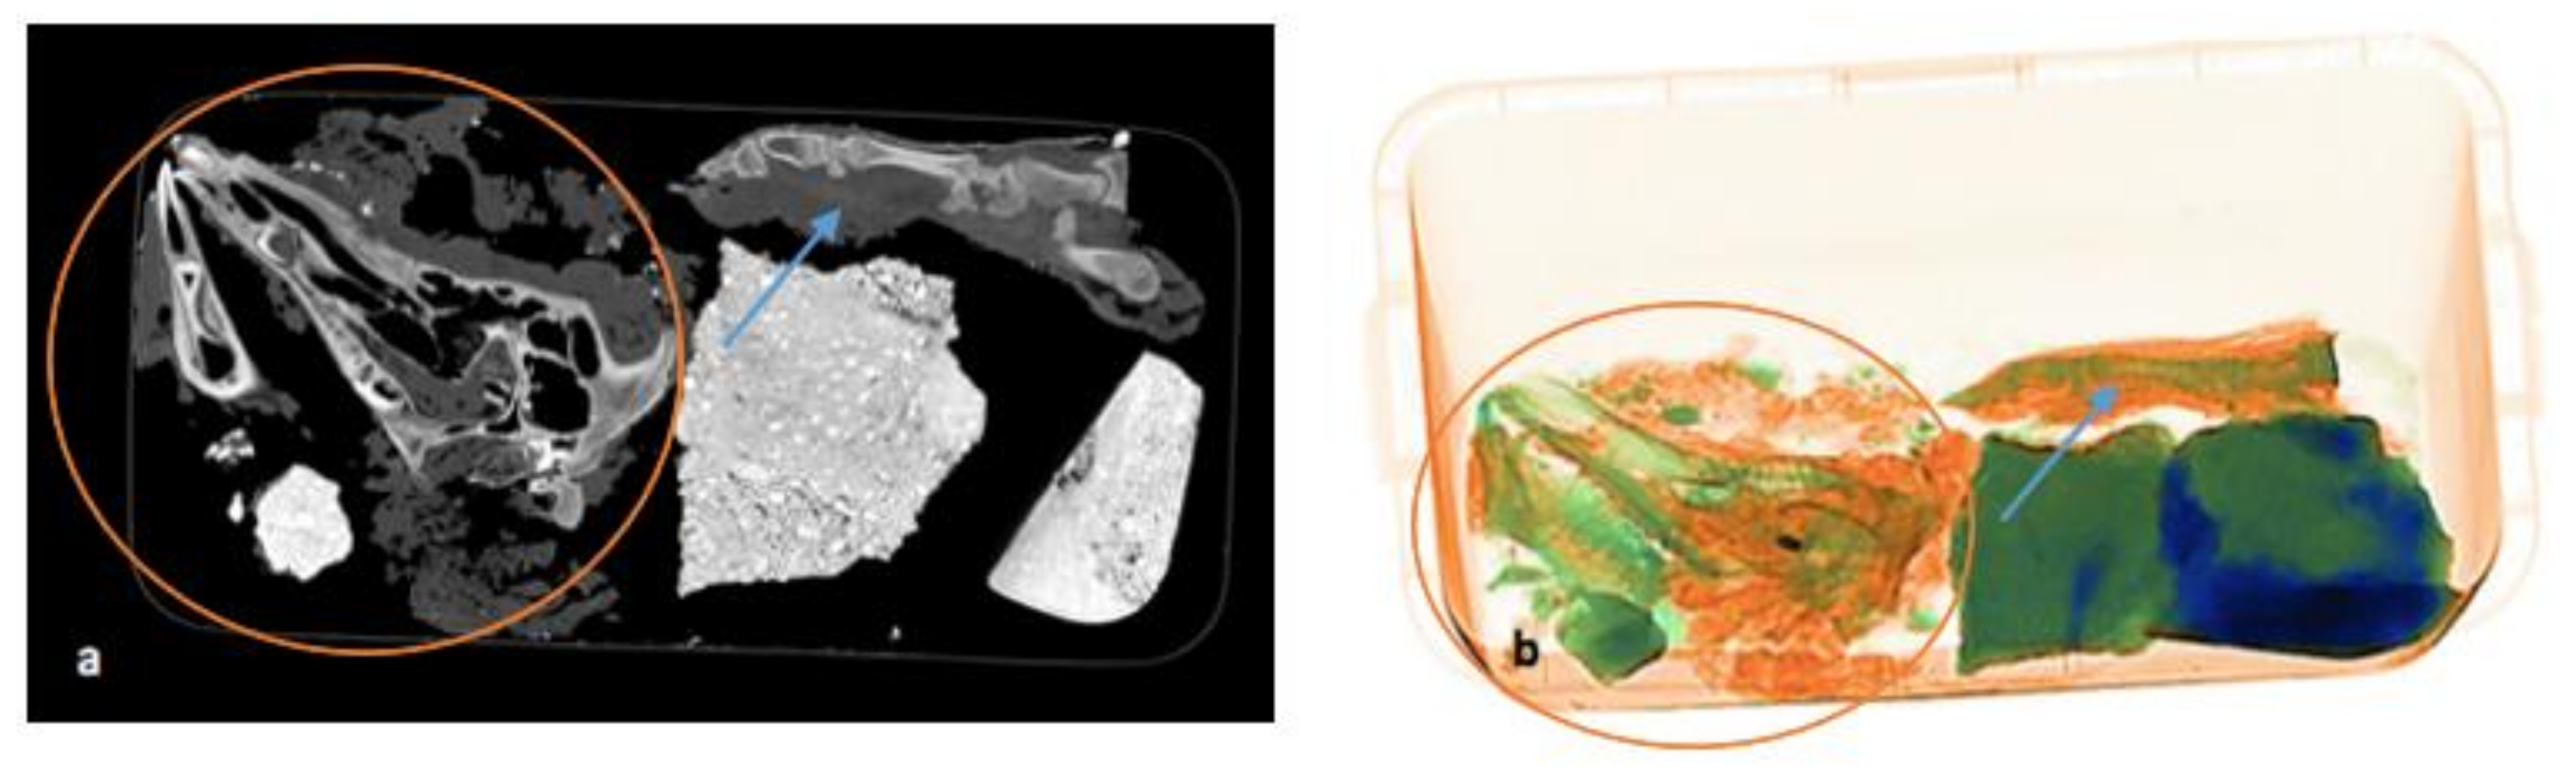

On the final pmCT/ X-ray image in Figure 7a,b, the paw is still intact, with bones and soft tissues around it. The bones of the head are disarticulated due to the disintegration of the soft tissue. The projectile is still visible in the orbit.

Figure 7.

(a,b) Comparison of pmCT (a) and X-ray image (b) on 14 September 2021 during the last scan. The disarticulation of the bones and disintegration of soft tissue (red circle) of the head and intactness of the paw (blue arrow) can be seen.